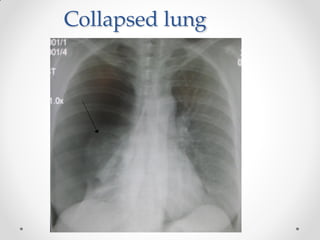

Clinical Relevance: Pneumothorax

• Pneumothorax (commonly referred to a collapsed lung) occurs when air

or gas is present within the pleural space. This removes the surface tension

of the serous fluid present in the space, reducing lung extension

• Clinical features:

• Chest pain, and shortness of breath, and asymmetrical chest expansion

• Upon percussion, the affected side may be hyper-resonant (due

to excess air within the chest)

• There are two main classes of pneumothorax

• Spontaneous

• Traumatic

• Traumatic: Occurs as a result of blunt or penetrating chest trauma, such as

a rib fracture (often seen in road traffic collisions).

• Treatment depends on identifying the underlying cause

• Primary pneumothoraces tend to be small and generally require minimal

intervention

• Secondary and traumatic pneumothoraces may require decompression to

remove the extra air/gas in order for the lung to reinflate (this is achieved

via the insertion of a chest drain)

Collapsed lung